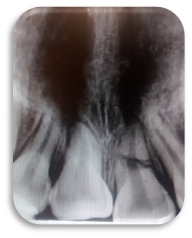

Se apreció lesión apical en la pieza 2.1 (imagen 1). Al realizar el acceso con una fresa bola de tallo largo #6 se tomó la radiografía de cavometría con la lima Flex R #20 a 20 mm (imagen 2), posteriormente se colocó pasta de hidróxido de calcio y se dejó durante un mes, después se tomó la radiografía de cronometría con cono #55. Se realizó la técnica de Crown Down para limpiar la parte coronal. Se instrumentó a partir de la lima #20 hasta la lima #55 master a 20 mm y se realizó retroceso hasta la lima #80. Al término del tratamiento se usó la técnica de condensación lateral combinada con vertical de gutapercha (imagen 3).

RESULTADOS

Después de siete meses se tomó una radiografía de control para verificar y revisar si hubo éxito clínico y se apreció como la lesión cedió totalmente. Para mejorar el tratamiento en boca de nuestro paciente fue preciso rehabilitar, con ayuda de un rehabilitador se procedió a colocar postes y coronas.

Imagen 1

Imagen 2

Imagen 3

Imagen 4